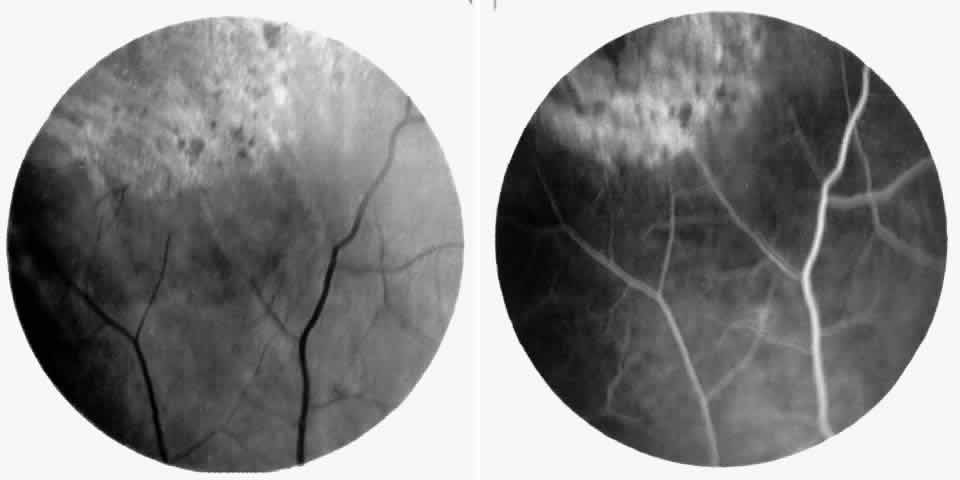

Angioid Streaks

Angioid streaks occur in association with sickle cell disease, with an overall incidence of less than 6%.72–75 The changes are more common in patients with homozygous sickle cell anemia and are age-dependent, occurring in 2% of sickle cell anemia patients less than 40 years of age versus 22% in those who are more than 40 years of age (Fig. 5).76

Fig. 5. A 45-year-old man with homozygous sickle cell anemia and angioid streaks (arrows).

Unlike the angioid streaks seen in patients with pseudoxanthoma elasticum, choroidal neovascularization and disciform disease are uncommon in association with sickle cell disease. Elastic tissue degeneration, as is seen in pseudoxanthoma elasticum, has not been demonstrated in the skin biopsy specimens of sickle hemoglobinopathy patients with angioid streaks.73,75 Initially, the etiology of angioid streaks in sickle cell disease was hypothesized to be secondary to iron deposition due to chronic hemolysis, causing brittleness of Bruch's membrane. Histopathologic examination of angioid streaks in a patient with homozygous sickle cell anemia, however, revealed heavy calcification of Bruch's membrane without evidence of iron or hemosiderin.77